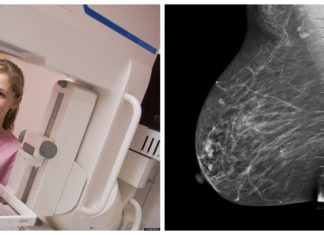

Искусственный интеллект в маммографии

На сегодняшний день проблема рака стоит достаточно остро. Ежегодно рак выявляется у нескольких сотен тысяч человек и главная проблема в том, что у многих он обнаруживается на поздних стадиях....